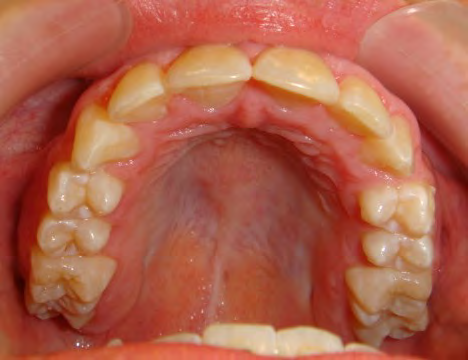

The patient below had severe crowding of both upper canines and the lower right 5. The upper 4’s and 2’s were actually in contact.

Below are cases treated at Vakresmil without extractions within the last three years. The families had been told, “It is simply not possible for your child to be treated without extractions” by orthodontists. Judge for yourself if that was right or wrong.